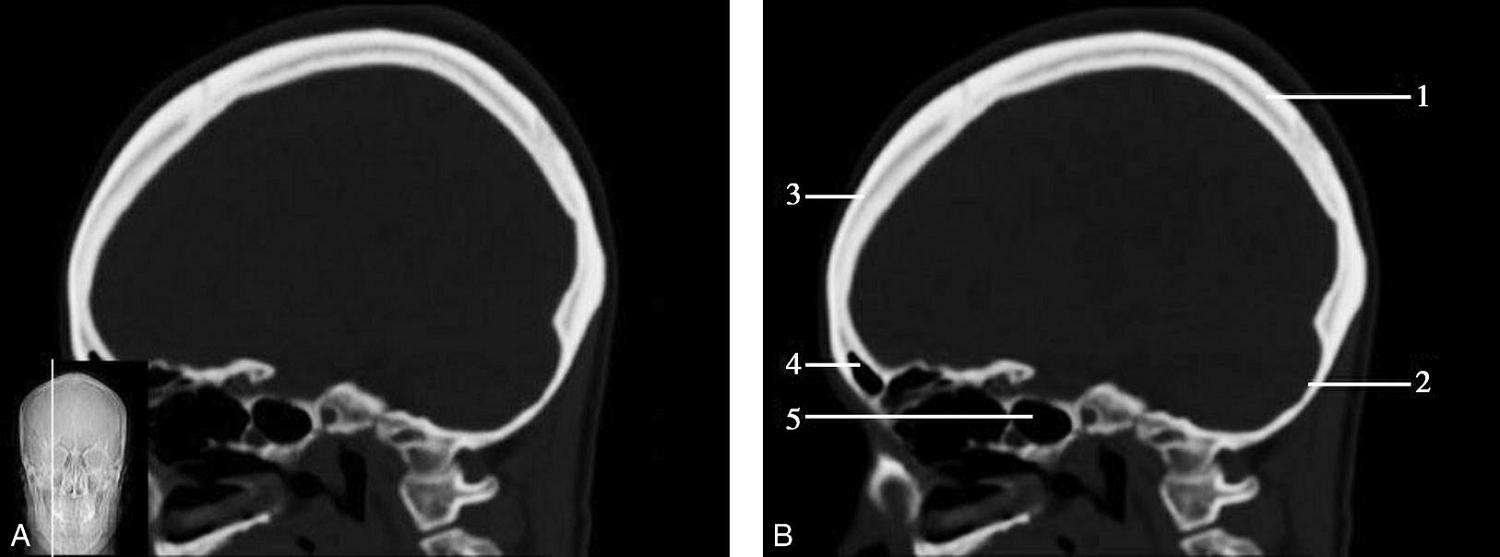

图1-2-60 正中矢状面骨窗CT

A.矢状面;B.矢状面标注

1.顶骨;2.枕骨;3.斜坡;4.额骨;5.蝶鞍